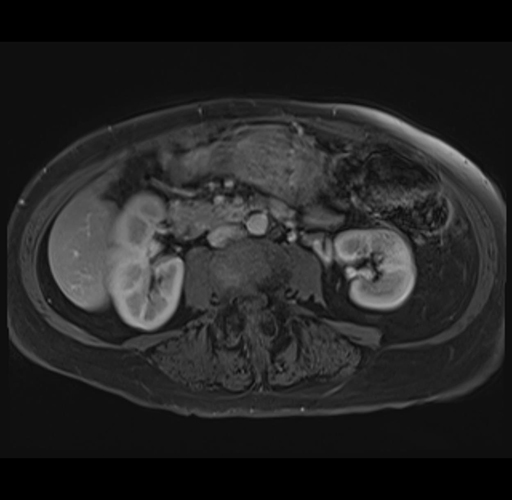

MRI T1